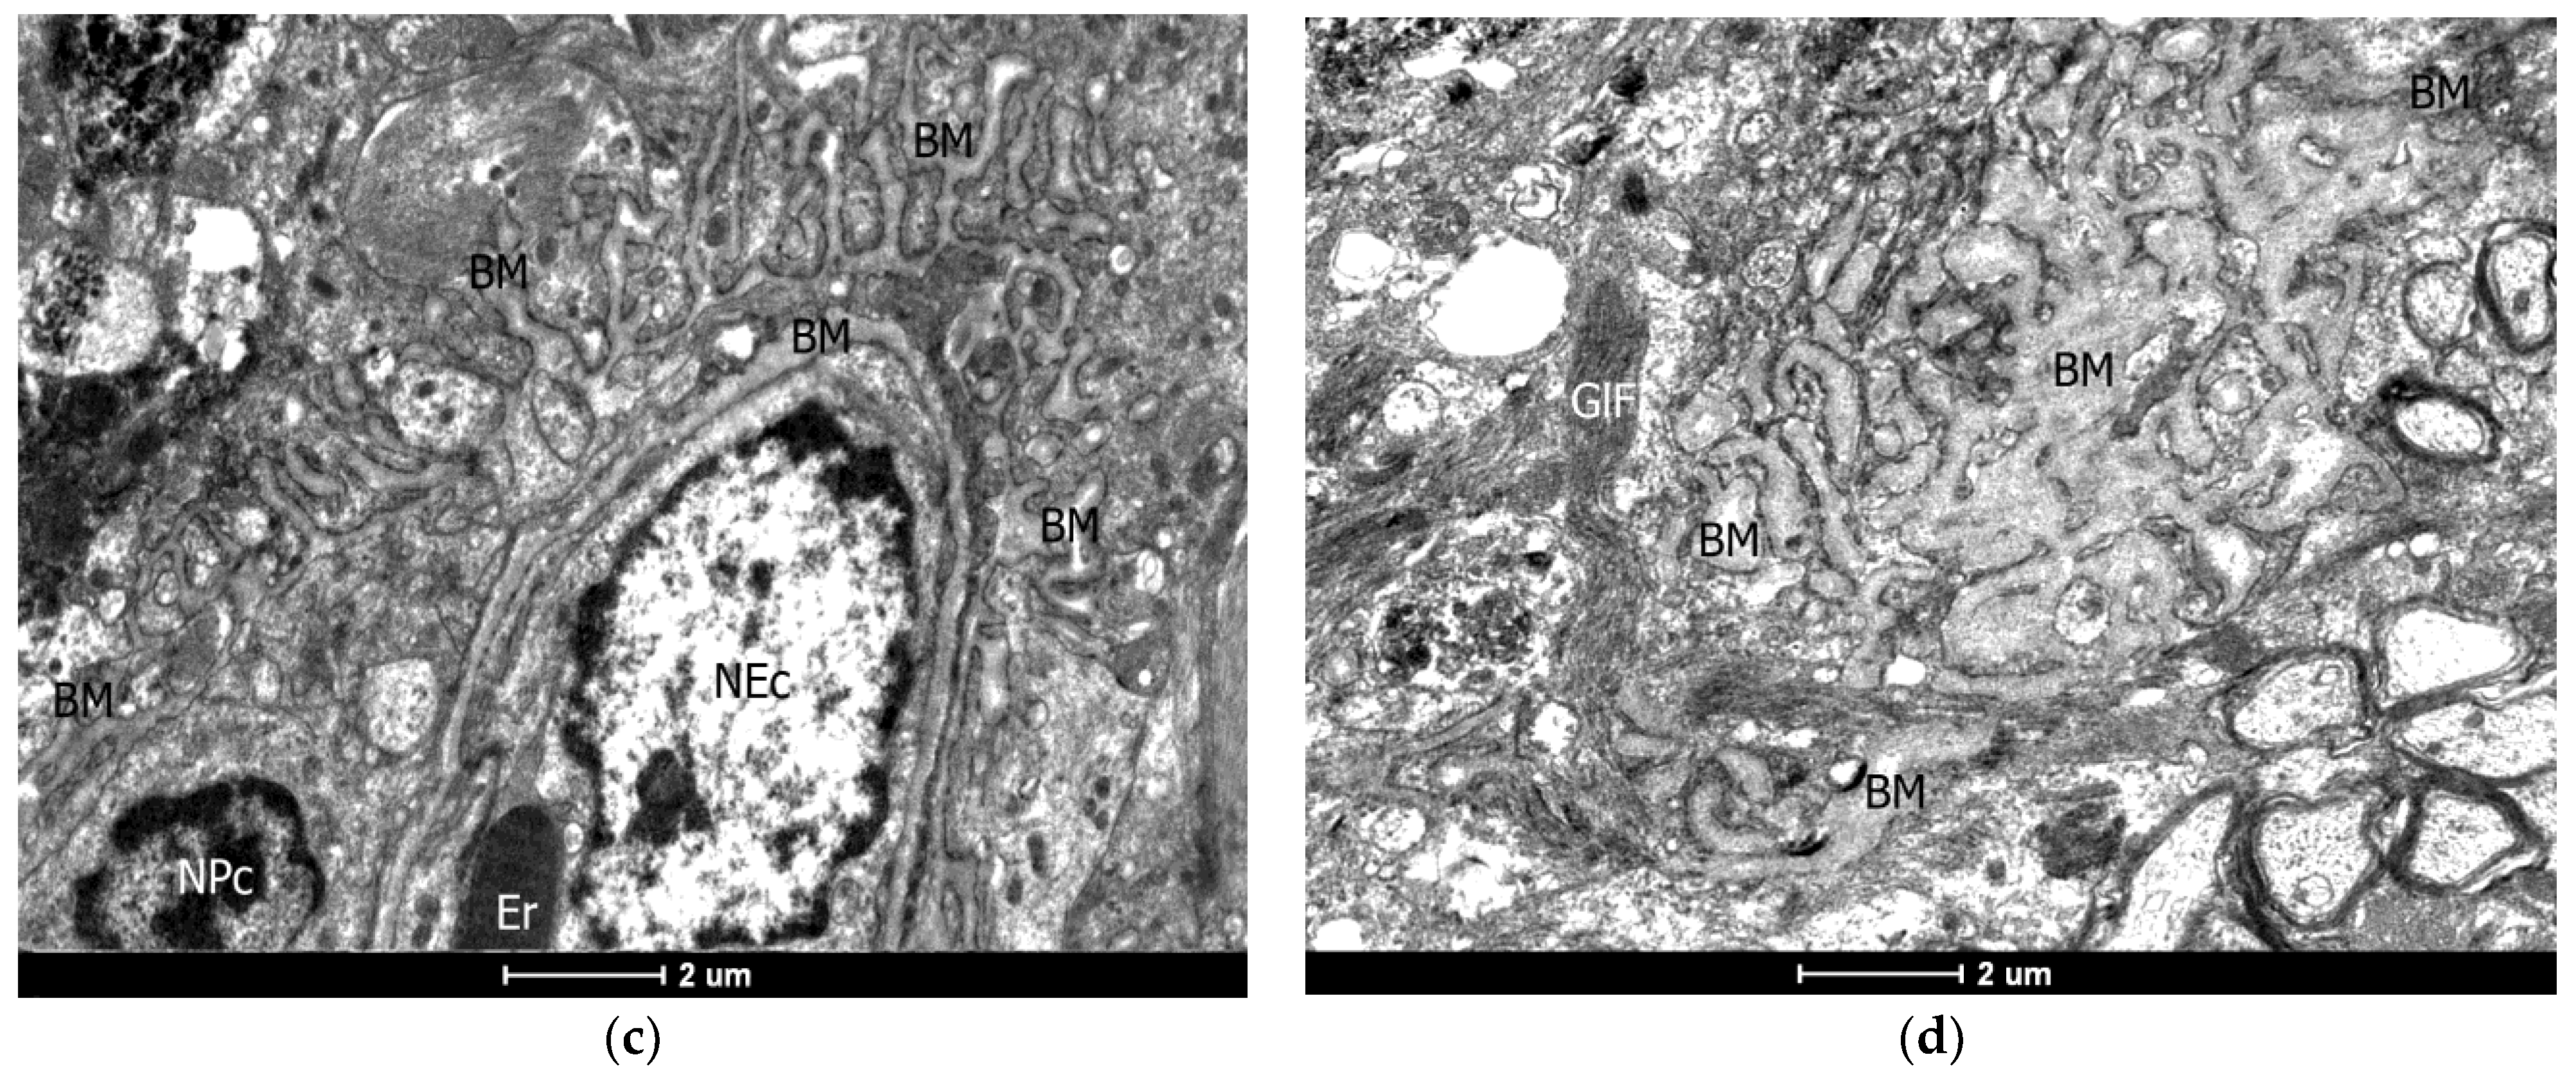

2.4. Ultrastructural (TEM) Examination of the Vascular Wall of the Capillaries

4.2. Transmission Electron Microscopy (TEM)

- Damage to BBB permeability in conditions of neuroinflammation is caused by endotheliocyte dysfunction with activation of angiogenesis (VEGF overexpression), stimulating the hyperproduction of basement membrane’s collagen and insufficiency of endothelial proliferation factors (EGF reduction);

- Observed malformation-like transformation of the basement membrane of the microcirculatory bed complicates the delivery of AEDs. Dysplasia of the basement membrane is the result of inadequate reparative processes in chronic inflammation.